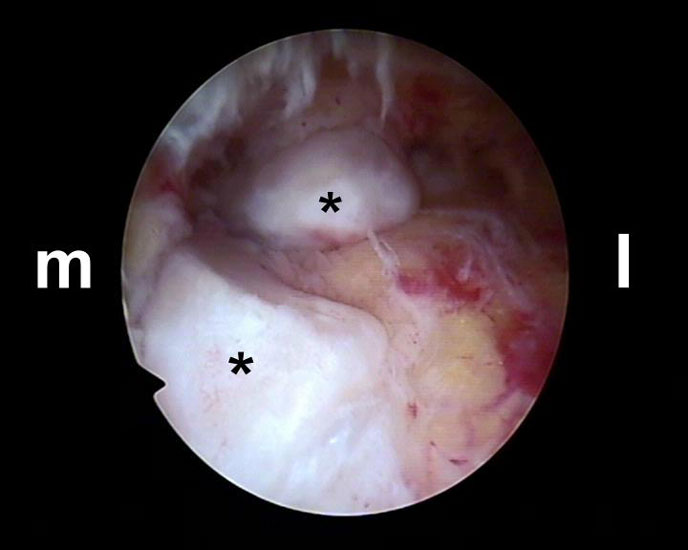

Es wird zunächst ein Weichteildebridement durchgeführt, bis die Flexor hallucis longus-Sehne identifiziert werden kann. Während des Debridements sollte auf die korrekte Ausrichtung der Instrumentenöffnung nach lateral geachtet werden. Im Verlauf empfiehlt sich der Wechsel auf eine bipolare Ablationselektrode, die eine gezielte Freilegung der Strukturen unter gleichzeitiger Blutstillung ermöglicht, ohne dabei unkontrolliert Gewebe anzusaugen (rechte Seite, m=medial, l=lateral). Das Os trigonum bzw. die Osteophyten sowie die FHL-Sehne müssen vollständig dargestellt werden (*=Os trigonum, FHL=Flexor hallucis longus-Sehne).

Abbildung Nr. 11-13

Das Os trigonum wird aus dem Weichteilgewebe gelöst und anschließend mit einer Fasszange entfernt. Bei größeren Knochenfragmenten muss ggf. das mediale Arthroskopieportal um wenige Millimeter verlängert werden, um die Extraktion zu ermöglichen. Nach Resektion des Os trigonum ist die posteriore Facette des Subtalargelenks erkennbar (rechte Seite, PF=posteriore Facette, FHL=Flexor hallucis longus-Sehne, T = Talus, K = Kalkaneus, *=Os trigonum).